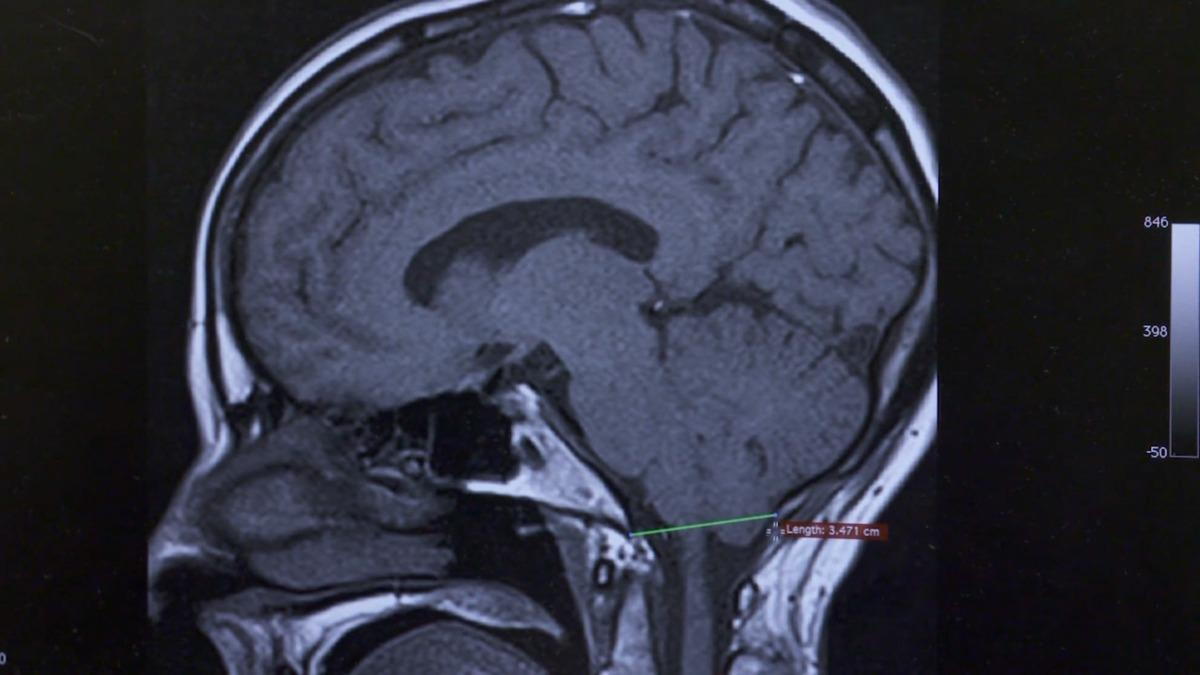

Chiari 0 malformation is a subtle variant within the Chiari family of disorders. Unlike more pronounced Chiari malformations, involving part of the brain protruding into the spinal canal, Chiari 0 typically shows less herniation on imaging tests, which is more subtle than a Medical Radiologist’s standard training. Consider the difference between a slightly inserted cork in a bottle of wine and a fully inserted cork. The observation is subtle. However, it still creates pressure at the base of the skull’s base, disrupting cerebrospinal fluid (CSF) flow and increasing pressure on nearby nerves and structures.